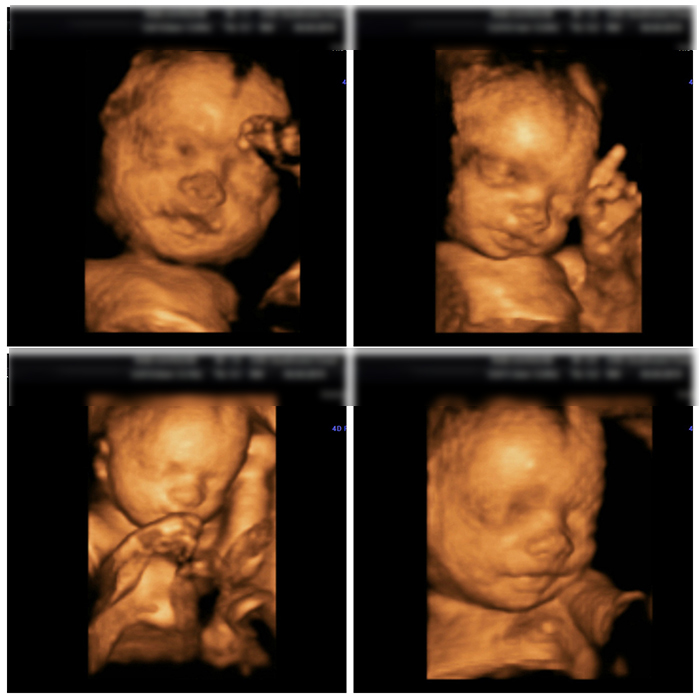

- Máy siêu âm hiện đại: Cơ sở nên sử dụng các dòng máy siêu âm kỹ thuật số, có độ phân giải cao, hỗ trợ các chế độ chuyên biệt cho sơ sinh (ví dụ: siêu âm Doppler màu, siêu âm 3D/4D).